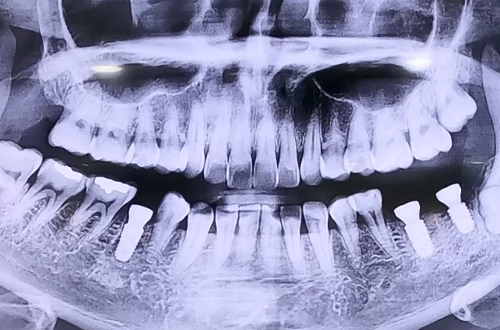

AFTER

발치한 자리에 바로 임플란트를 진행하였으며, 치료하며 보니 잇몸이 손상되어 있어

임플란트가 단단히 자리 잡을 수 있도록 뼈 이식을 함께 한 케이스입니다.

발치 후 즉시 임플란트 시에는 이를 뺀 자리에 구멍이 남기 때문에, 잇몸 안쪽으로

음식물 등의 이물질이나 세균이 들어가지 않도록 뚜껑을 덮어 마무리합니다.

본 케이스는 임플란트가 자리 잡기까지 4개월 정도 기다린 후,

보철이 예쁘게 완성되면 다음 진료일지로 찾아뵙도록 하겠습니다~ ^^